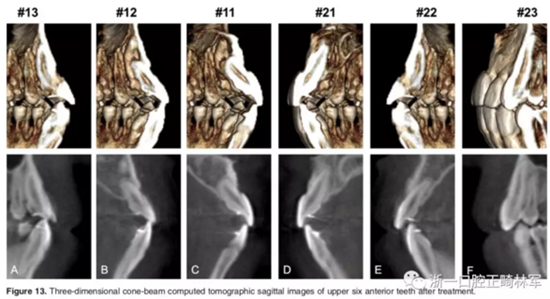

影像學(xué):頭顱側(cè)位片示:矢狀向和垂直向骨骼發(fā)生變化(ANB角,3°;SN-MP,51°);上頜切牙略前傾(U1-SN,106°),與下頜切牙一致(IMPA,75°);病人的面部輪廓得以保持。全景片示:由于牙齒萌出,上前牙區(qū)垂直向牙槽骨水平增加;雖然前牙牙根較彎曲,但其平行度仍可,且無(wú)明顯的牙根吸收。CBCT示:前牙唇側(cè)骨質(zhì)連續(xù)性改善,牙根唇側(cè)支持組織變好,牙槽骨高度、厚度均有增加,但轉(zhuǎn)矩的改變一定程度上導(dǎo)致了局部應(yīng)力的增大。